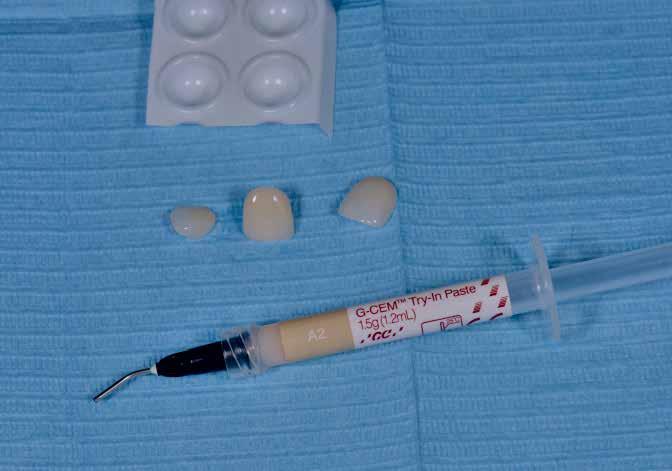

A páciens tehát nem fogadta el az implantátumos megoldást. Van másik lehetőség? Igen – cirkóniumoxid híd. A szakirodalom alapos áttanulmányozását és több szakember megkérdezését követően kerámia ellátást terveztünk, ovális köztes felfekvővel. A páciens ebbe beleegyezett.

Visszafelé tervezéssel kívántuk megoldani a szituációt – meghatározva a kezelés végeredményét, abból kiindulva tervezni. Tudatosan nem tárgyalom itt a részleteket, mert cikkem arra koncentrál, hogyan készült a híd a tojásdad felfekvőkkel. Természetesen elengedhetetlen jó felvételek készítése, majd a teljes viaszmintázat képezi a további munka alapját. Ugyancsak „kötelező” a korrekt harapás alapján végzett analízis. A héttagú cirkon hidat a Pritidenta cég anyagából készítettem. Gondoltam a nagymértékű szilárdságra, magas E-Modulra. Az ötletet évek óta velem a Geiger Frézközpontban együttműködő partnerem, a bettringeni Peter Hölldampf fogtechnikusmester adta.

Az ekkor készült lenyomat alapján köztes lépésben multicolor PMMA CAD/CAM ideiglenest készítettünk, az esztétikai lehetőségek ellenőrzésére. Már ebben a stádiumban nagy jelentőséget tulajdonítva annak, mértük az alveolust. Ezt a munkát Hans-Peter Vögtle fogtechnikusmesterrel közösen készítettük schluchsee-i laboratóriumában. Az orvosi ideiglenest levettük, és bepróbáltuk a PMMA-t. Fontos ez a köztes lépés, hogy mindent még egyszer ellenőrizhessünk, így adva lehetőséget a páciensnek a végleges kinézetének meghatározására (18–25. képek)